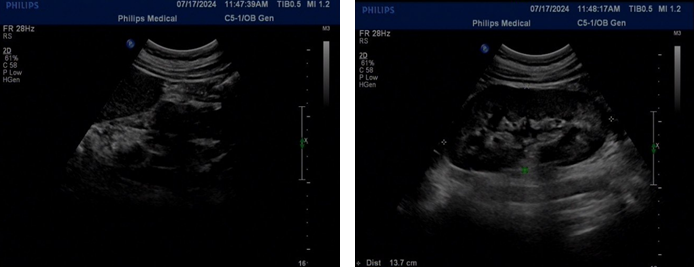

ultrasound (2024-07-15): Didelphic uterus (single cervix, single cervical

canal) with multiple fibroids in the left uterus, the largest measuring

approximately 454437mm, one of which is submucosal, adenomyosis with fibroids

in the right uterus, a small amount of fluid in the right uterine cavity, and a

poorly echoic area on the right measuring 74×57×32mm, suggesting the possibility

of hydrosalpinx (Figure 2). On July 16, 2024, the patient's CA-125

Figure 2: Expert ultrasound. The left image is the left uterus, and the right

image is the right uterus.